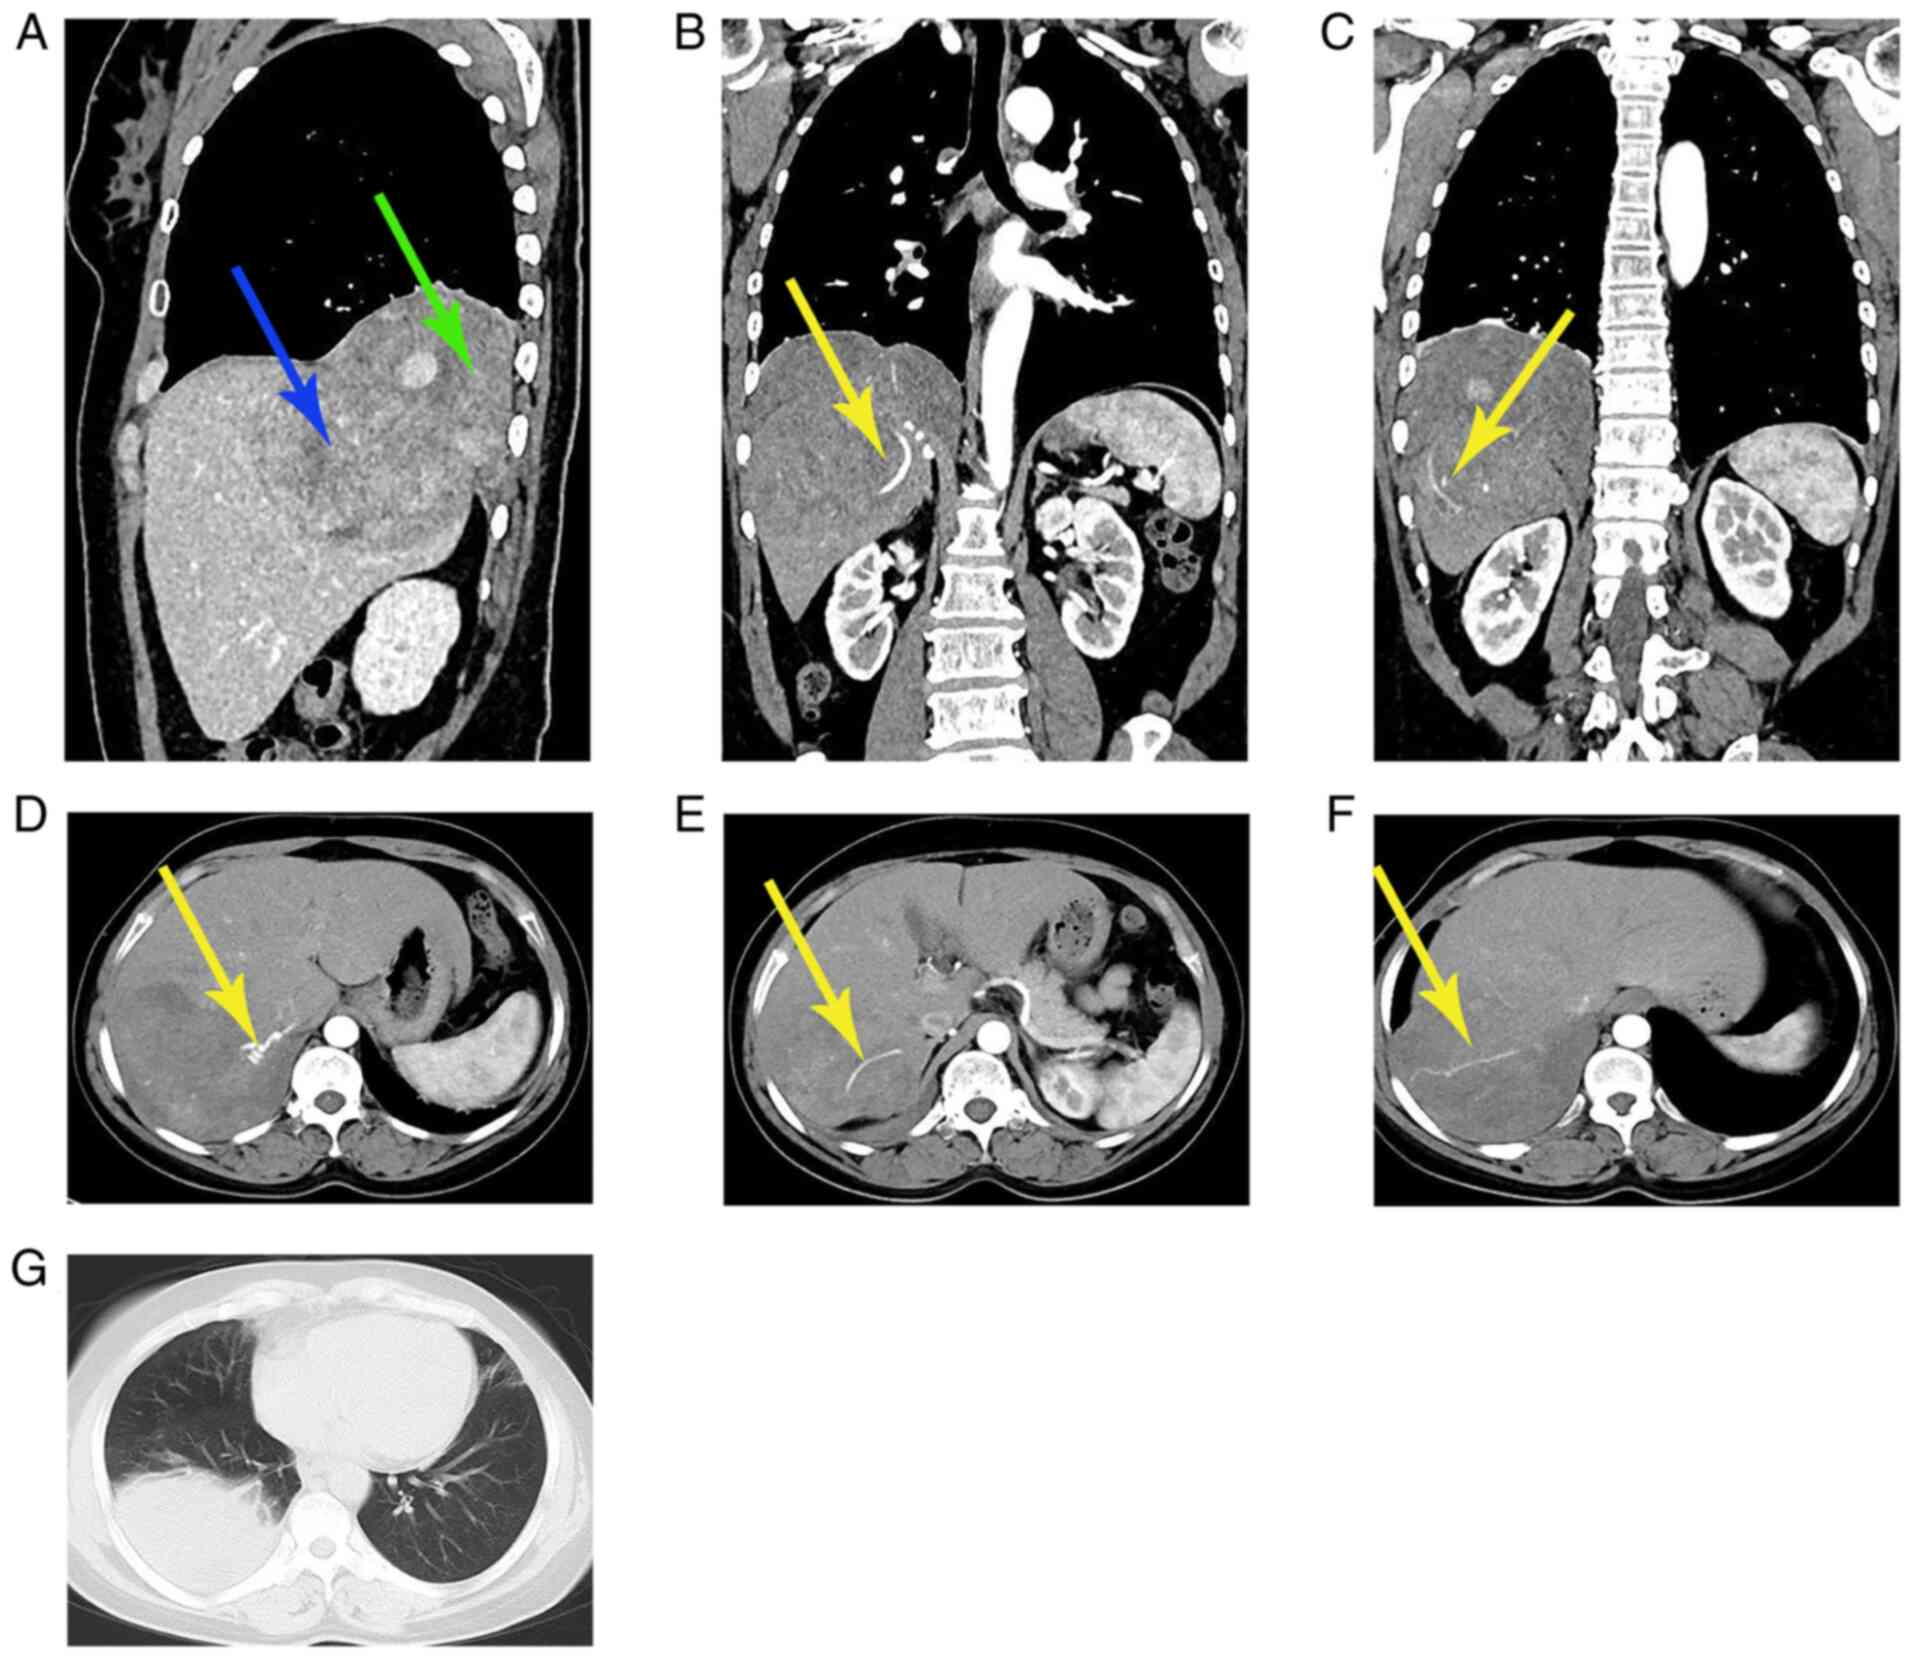

Multidisciplinary collaboration for the successful treatment of a giant hepatic solitary fibrous tumor protruding into the thorax: A case report

Solitary fibrous tumors (SFTs) are composed of spindle cells and collagen fibers, and these form rare mesenchymal tumors. SFTs are most frequently observed in intrathoracic sites; however, they may also occur in extrathoracic sites, such as the liver. Unlike the hepatic SFTs (HSFTs) reported in the literature, the SFT detailed in the present case report was a large tumor that originated from the liver, with a dumbbell‑shaped growth through the diaphragm into the right thoracic cavity. This posed substantial challenges in both diagnosis and treatment. Thus, the present report outlines the findings of a multidisciplinary team meeting that was used to discuss and develop an optimal and personalized treatment strategy for the patient. Transhepatic arterial embolization was performed to block the major arterial blood supply to the tumor in order to reduce its size. Subsequently, the tumor was fully resected, following the collaboration of the experienced hepatobiliary and thoracic surgeons. Following surgery, the abdominal distension experienced by the patient ceased, and no tumor recurrence was detected at the 1‑year follow‑up. In conclusion, due to limited previous reports of HSFT treatment using multidisciplinary collaboration, the present study outlined the treatment used for this specific tumor type, and the corresponding literature was reviewed.